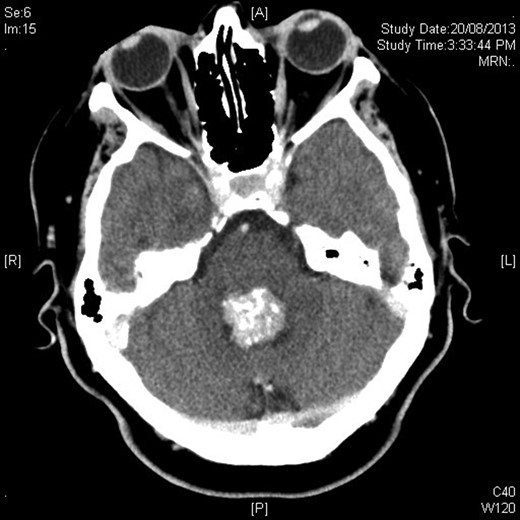

Mrs MM is a 62-year-old female who presented to our institution complaining of a 4-day history of nausea, vomiting and speech difficulties. She initially presented to a peripheral hospital following a fall at home and underwent workup for this. Clinically she scored a Glasgow Coma Scale (GCS) of 14 due to her confusion but had normal strength in all of her limbs. Initial computed tomography brain revealed a 2.6 × 2.5 × 2.1 cm rounded masses enhancing with contrast with areas of calcification in the fourth ventricle and obstructive hydrocephalus (Figs 1 and 2). The following day she underwent magnetic resonance imaging (MRI) brain showed the lesion to be isodense on T1-weighted imaging mildly hypodense on T2-weighted imaging (Fig. 3), and there was no other pathology demonstrated apart from chronic microvascular ischemic changes.

Axial contrast-enhanced CT showing hyperdense rounded lesion in fourth ventricle.